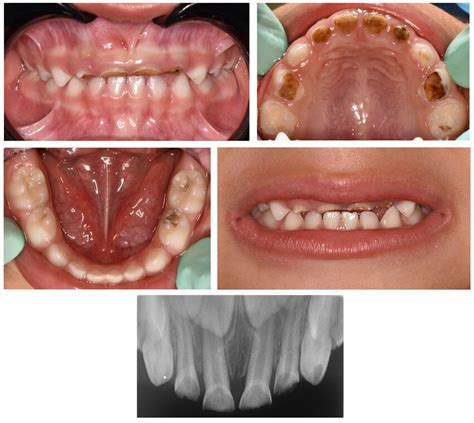

2. Fotografías Intraorales

Las fotografías intraorales nos sirven para ver tamaño y posición de dientes, si hay apiñamiento o espaciamiento entre éstos, la relación entre arcadas (resalte, sobremordida, mordida cruzada, mordida en tijera…), la relación canina o molar, valorar la línea media.